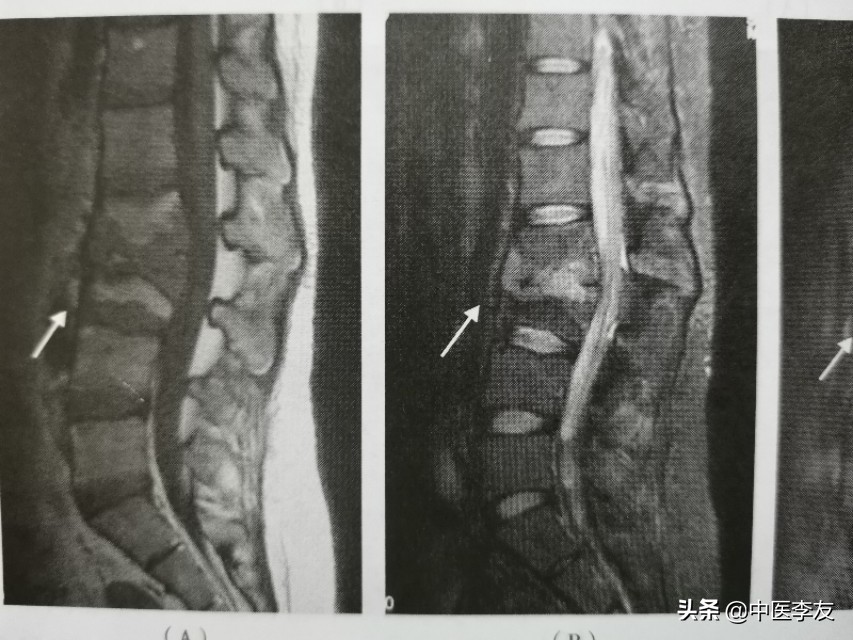

3.MRI,表现是显示脊椎结核病灶和范围最敏感的方法,可发现椎体内早期炎性水肿。病灶T1WI表现为低信号,T2WI多表现为混杂高信号;GD-DTPA增强不均匀强化。脓肿和肉芽肿在T1WI上呈低信号,T2WI多为混杂高信号,部分均匀高信号,增强检查肉芽肿不均匀,均匀强化,脓肿壁薄且均匀的环状强化。

在脊柱结核发病的时候,一般有两种类型:①中央型,病灶起于椎体松质骨,死骨吸收后形成空洞。②边缘性,病变破坏椎体边缘和椎间盘组织,椎体呈楔形破坏,椎间隙变狭窄,形成脓肿,继而形成椎旁脓肿,并向组织间隙流向远处。

②椎间隙变窄或消失,因椎间盘及软骨终板被破坏,椎间盘破坏严重者可导致相邻的椎体融合在一起,为诊断脊椎结核的重要依据。

③后突畸形:为脊椎结核较特征性表现之一,为多个椎体明显破坏所致。